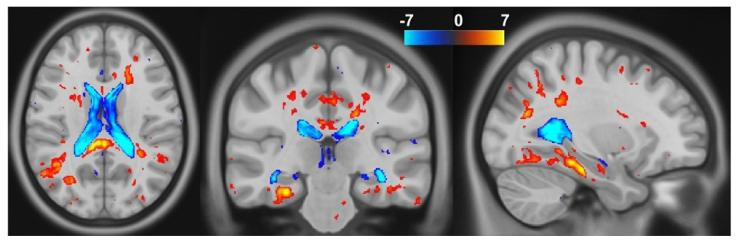

Fig. 7. T-test results on the Jacobian determinants between healthy controls andAlzheimer’s disease subjects, computed using USLR. We show the t-values thresholdedat 𝑝 = 0.05 corrected for multiple comparisons using FDR.

图7 使用USLR计算的健康对照者与阿尔茨海默病受试者之间雅可比行列式的t检验结果。图中展示的t值以𝑝=0.05为阈值(通过虚假发现率(FDR)校正多重比较)。